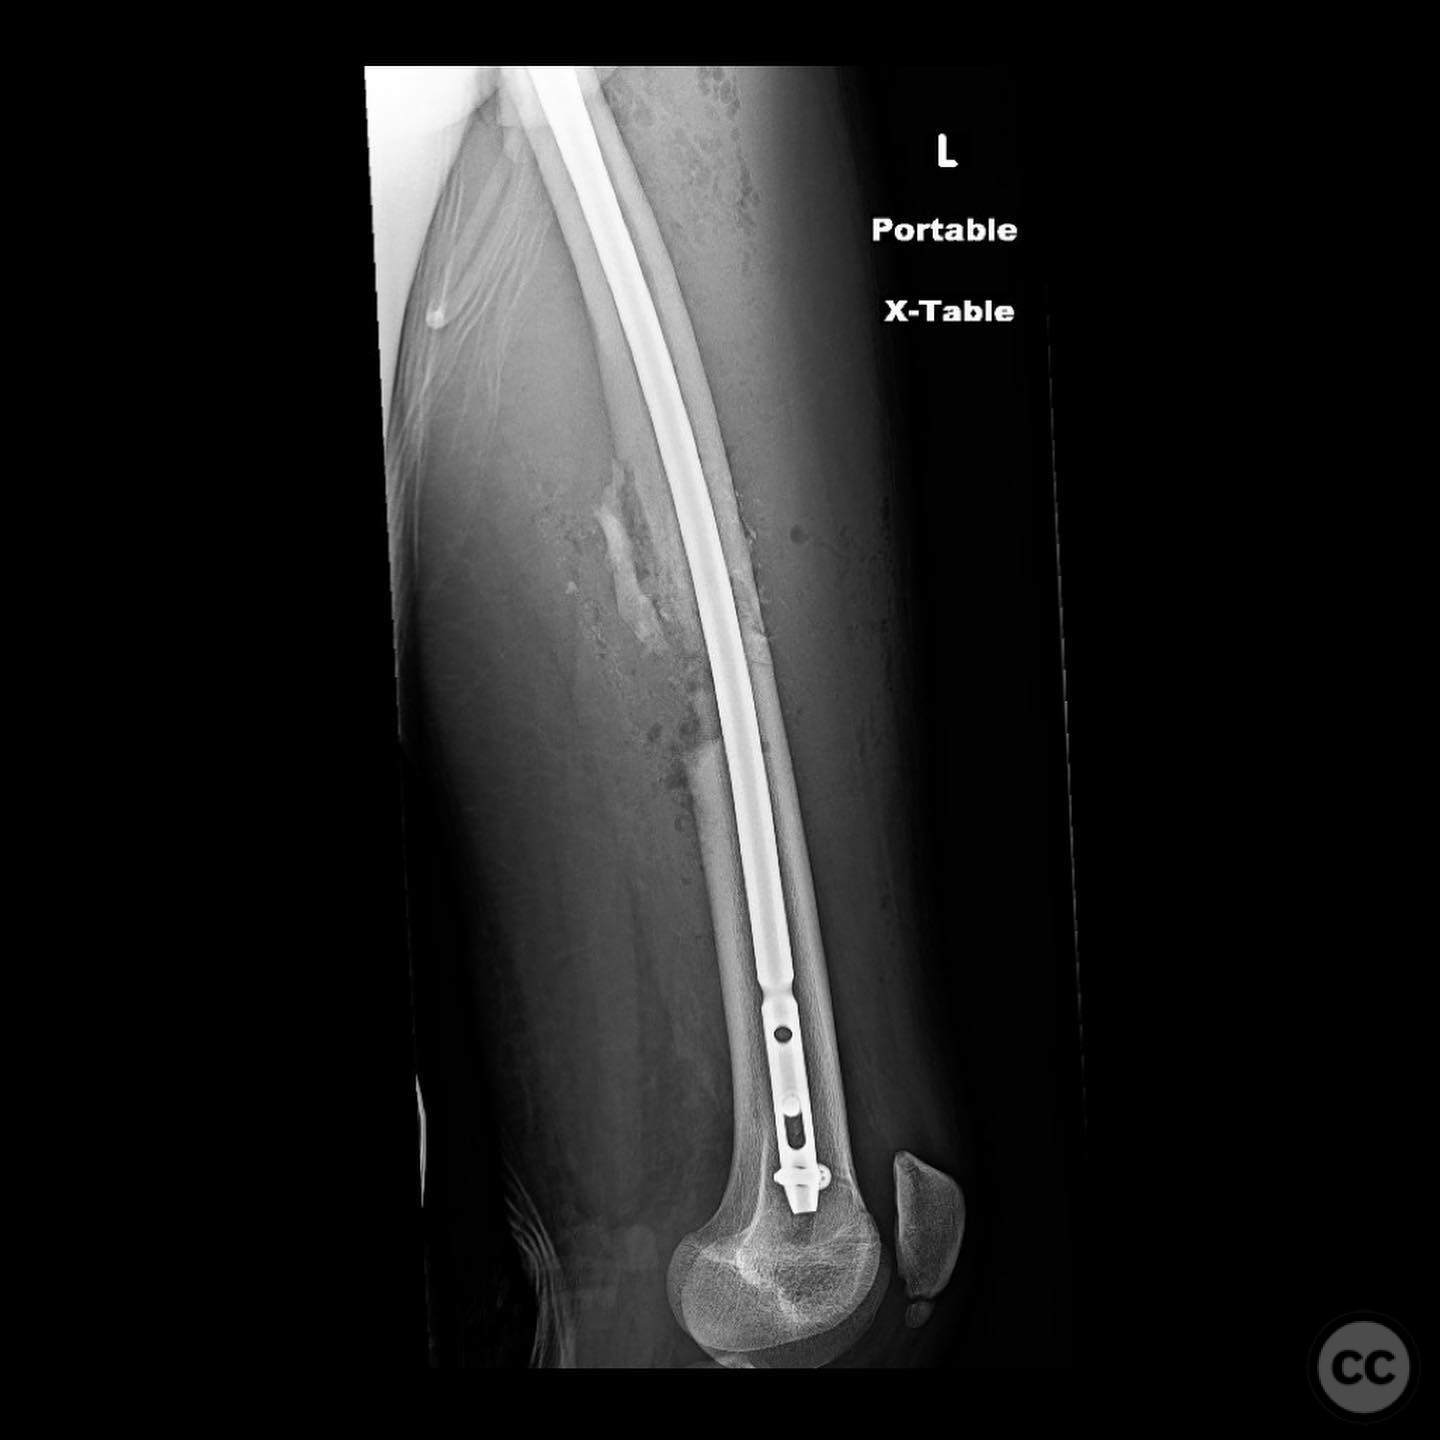

Comminuted Diaphyseal Femur Fracture in a 16-Year-Old

Clinical and radiological findings:  A 16-year-old male sustained a comminuted diaphyseal femur fracture after a 50-foot fall while rock climbing. The patient presented with multiple injuries but was well resuscitated and cleared for surgical treatment of the femur fracture within 24 hours. The injury was closed, with no neurological or vascular compromise noted.

Planning remarks:  The preoperative plan involved an open reduction and internal fixation (ORIF) due to the complexity of the fracture and the presence of a large incomplete napkin ring segment that could not be managed with closed nailing techniques. The anatomical approach was planned through a lateral incision to allow direct access to the fracture site for reduction and fixation.

Orthopaedic implants used:   Intramedullary nail, autologous bone graft from reamings.